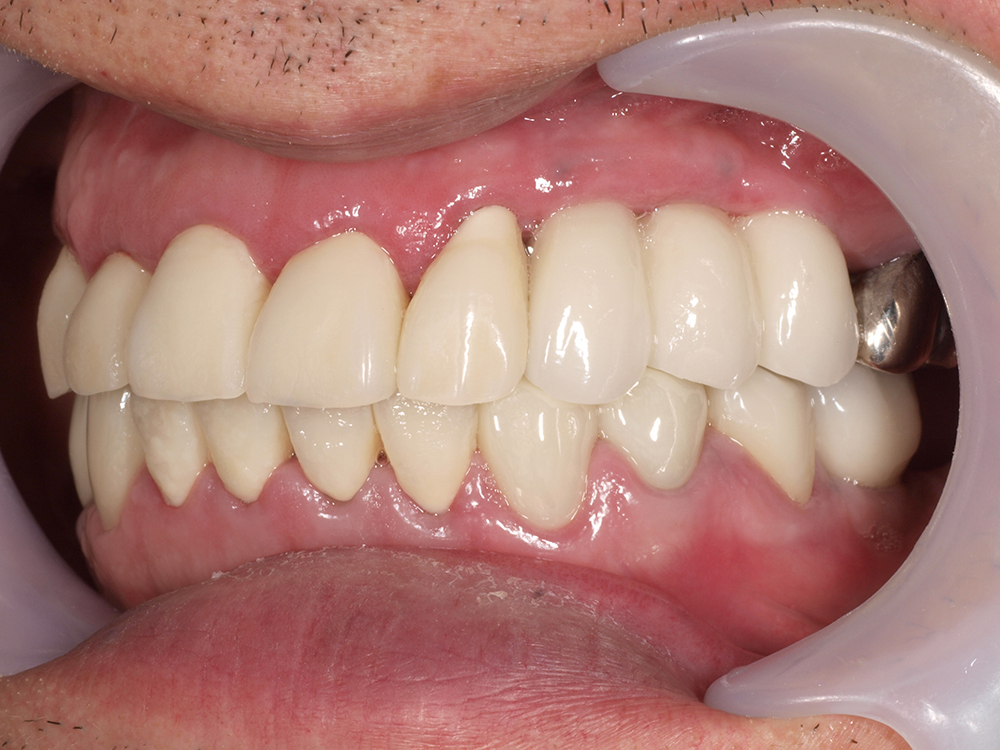

53歳 男性

- 主訴

- 全然噛めない。上の歯が取れてきた

- 処置内容

- 上顎:8本 下顎:2本

- 治療費用

- 上顎:約320万円(税込)、下顎:約160万円(税込)

- 治療期間

-

上顎:1年(仮歯まで8か月)

下顎:8か月(仮歯まで5か月)

- リスク

- 上部構造物、仮歯の破折、術後の腫れ(3日)、人工歯根脱落リスクがあります